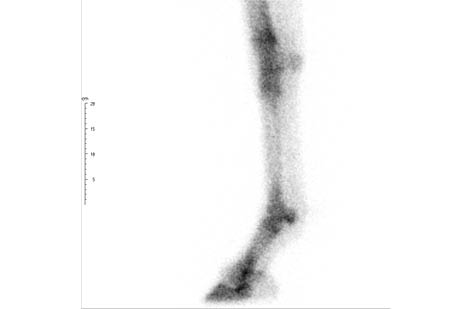

Motion Correction on the Fly

Innovative Imaging Technology

To minimize motion artifacts for the standing horse, MiE has developed the world’s first real-time motion correction. The rigid registration software allows shorter image acquisition times and improved diagnostic quality. Using the ParalyzerPLUS software eliminates the need to repeat acquisitions.

Real-Time Motion Correction: Faster Scans, Enhanced Quality

ParalyzerPLUS

ParalyzerPLUS raw study

raw study ParalyzerPLUS

ParalyzerPLUS raw study

raw study ParalyzerPLUS

ParalyzerPLUS raw study

raw study ParalyzerPLUS

ParalyzerPLUS raw study

raw studySelection of possible studies